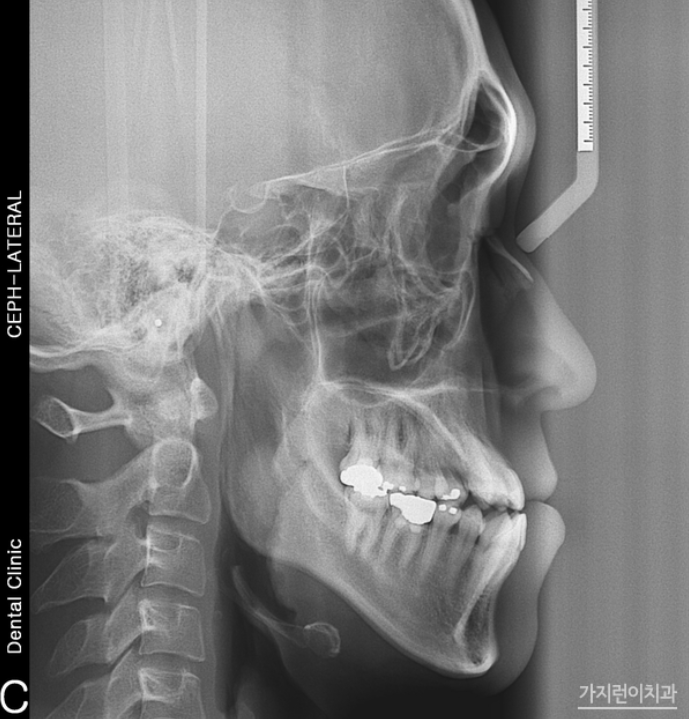

상단의 사진의 경우 주걱턱 케이스인데요. 아래턱이 유독 튀어나온 경우임에도 수술 없이 치아교정을 통해 개선한 경우입니다. 치료에 앞서 발치를 진행하는 것 만으로도 충분히 아래 턱을 집어넣을 수 있다고 판단했기 때문인데요. 결코 무리한 과정이 아닌 가능하다고 판단했기 때문에 진행했기 때문에 안정적으로 진행해볼 수 있었습니다. 효과적으로 치아를 후방이동 시키기 위해 미니 스크류를 식립한 후 교정용 고무줄을 연결했는데요. 주걱턱 양상과 덧니까지 함께 관찰이 되었다면 측면에서 관찰해도 정상교합으로 맞춰질 수 있도록 플랜을 구성해 니즈를 충족하고 있습니다. 특히 주걱턱, 덧니의 경우 이미지 변화가 큰 편인데요. 만족스런 결과를 보고 나도 해볼까? 라는 생각이 든다면 미리 상담 예약 후 방문해 도움 받아보시기 바랍니다.